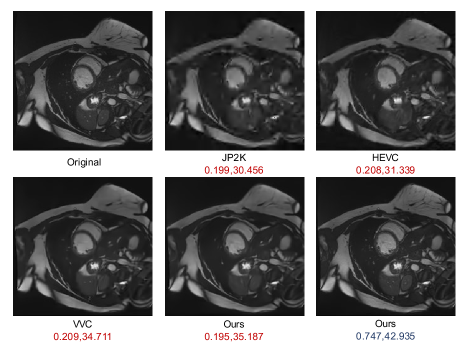

Refer to caption

Figure 7: Comparison of reconstruction quality for human vision on the ACDC dataset with compression results (BPP, PSNR).

The DICE coefficient is commonly used to calculate the similarity between ground truth and prediction in medical image segmentation. The Our Latents method demonstrates an improvement in DICE performance in our experiments. For example, as the bits per pixel (BPP) increases in the CHAOS dataset, the DICE performance of all three compression methods shows an upward trend. At the same compression rate, the Our Latents method achieves higher DICE scores than both the Our Image method and JP2K. Similarly, on the Synapse dataset, the DICE scores achieved by the Our Latents method are higher than those of JP2K across multiple BPP values. Notably, as illustrated in Fig. 8, the Our Latents method significantly improves segmentation performance at low BPP. We conduct further analysis on this phenomenon. From the reconstructed images shown in Fig. 7, it can be observed that our method, based on autoencoders, produces clearer edge information under high compression ratios and low BPP situations. This greatly aids downstream segmentation networks in extracting organ edges, resulting in more accurate mask predictions. Additionally, reconstructing images clearly at low BPP is a significant challenge for the reconstruction network. Suppose our latent decoding features already contain sufficient information about the original images, but the reconstruction network is limited in its ability to recover a clear image, which explains why the DICE score of Our Latents method surpasses that of the Our Image method.